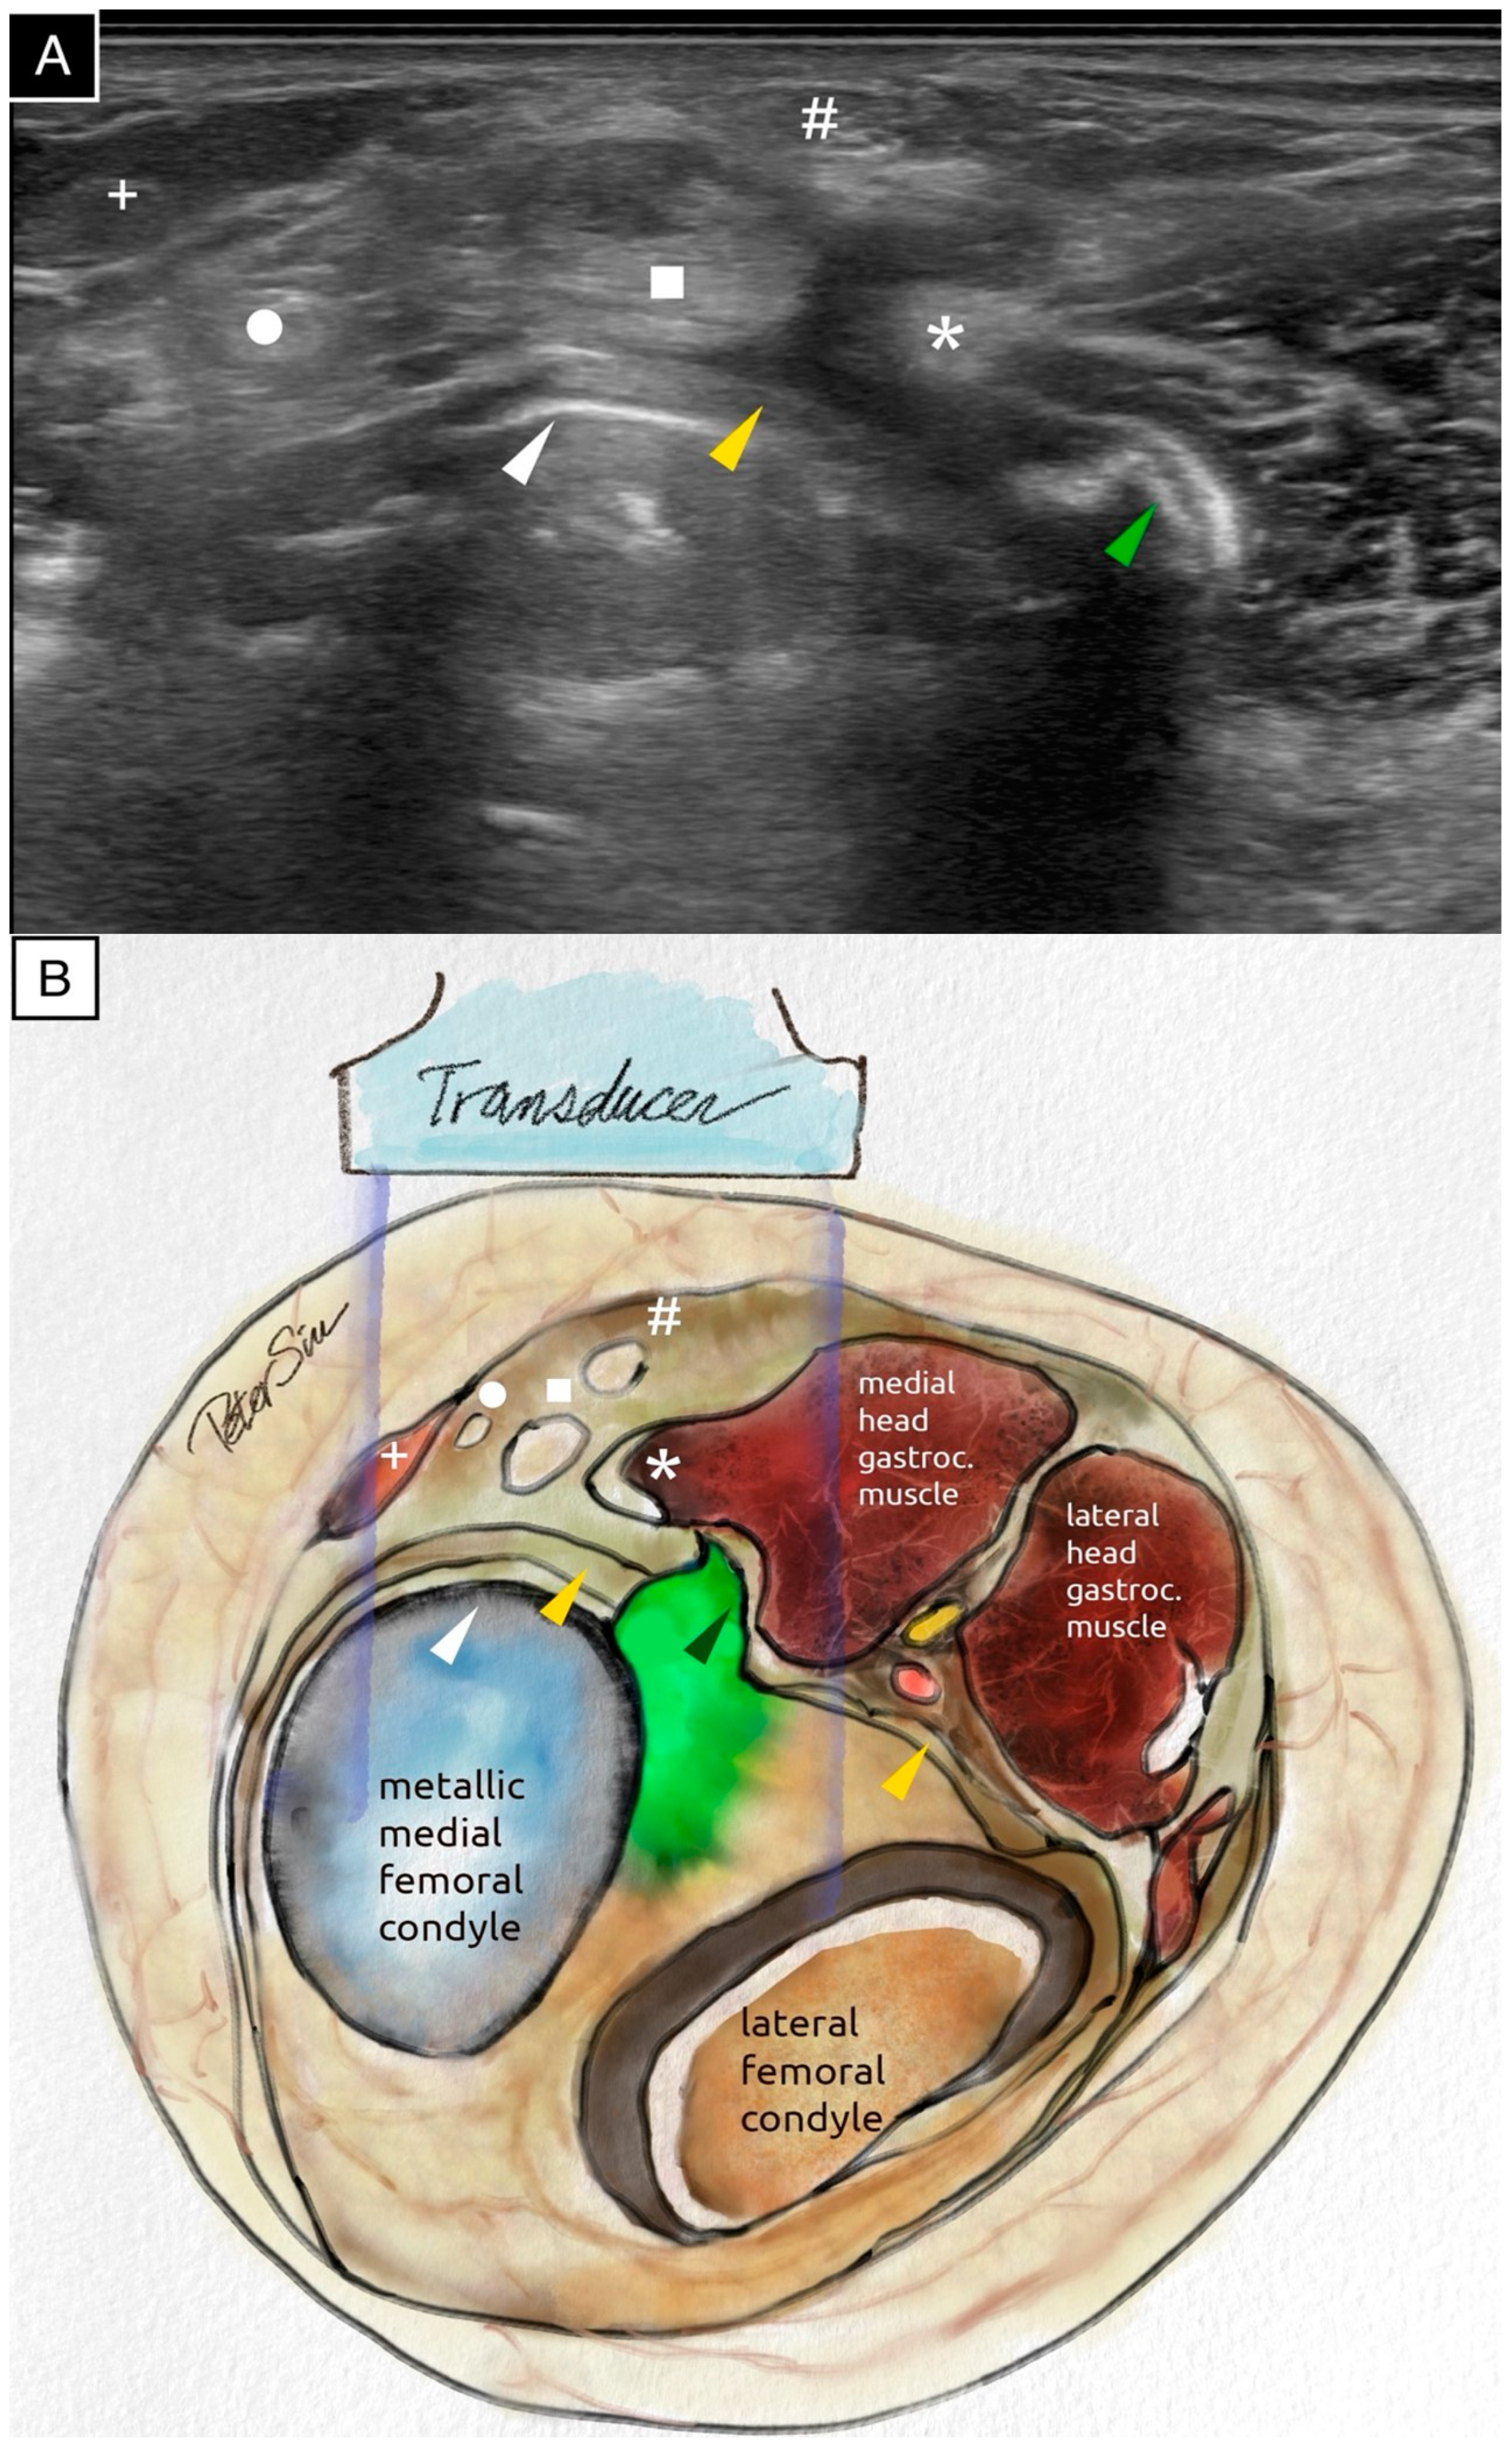

Figure 2. The transverse ultrasound scan (A) and the schematic illustration (B) of the posteromedial knee demonstrate extruded cement positioned posterior to the metallic femoral component. The extruded cement impinges on the posterior capsule and the medial head of the gastrocnemius muscle. The surface of the extruded cement reflects ultrasound waves, producing a surface echogenic line and casting a strong posterior acoustic shadow. The following anatomical structures are labeled: the extruded cement (green arrowhead), the posterior capsule (yellow arrowhead), the posterior border of the metallic femoral component (white arrowhead), the medial head of the gastrocnemius muscle (asterisk), the semimembranosus tendon (square), the gracilis tendon (circle), the semitendinosus tendon (hash sign), and the sartorius tendon (plus sign). The ultrasound image, acquired using the Fujifilm Sonosite PX with an L15-4 linear probe (operating at the general frequency setting, with the dynamic range set to 0 on a scale from −3 to +3, and the time gain compensation kept at the factory setting with no adjustments), provided a detailed assessment of the surrounding soft tissues and highlighted the extensive application of ultrasound technology in the medical field [1]. An ultrasound evaluation is provided in Video S1.

Diagnostics 15 00112 g002